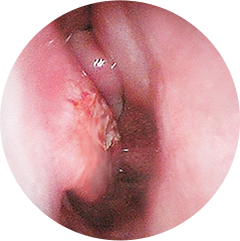

Rhinitis (Nasal Congestion)